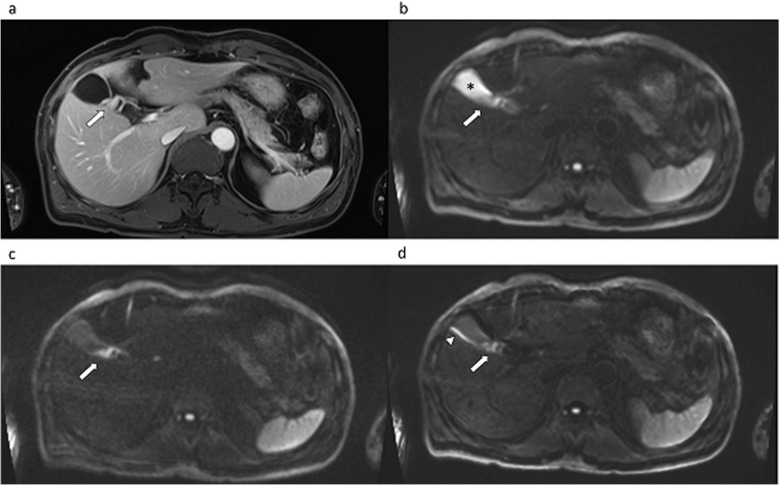

Purpose: Although diffusion-weighted imaging (DWI) with ultra-high b-values is reported to be advantageous in the detection of some tumors, its applicability is not yet known in biliary malignancy. Therefore, this study aimed to evaluate the impact of measured b = 1400 s/mm2 (M1400) and calculated b = 1400 s/mm2 (C1400) DWI on image quality and quality of lesion discernibility using a modern 3T MR system compared to conventional b = 800 s/mm2 DWI (M800).

Methods: We evaluated 56 patients who had pathologically proven biliary malignancy. All the patients underwent preoperative or baseline 3T MRI using DWI (b = 50, 400, 800, and 1400 s/mm2). The calculated DWI was obtained using a conventional DWI set (b = 50, 400, and 800). The tumor-to-bile contrast ratio (CR) and tumor SNR were compared between the different DWI images. Likert scores were given on a 5-point scale to assess the overall image quality, overall artifacts, ghost artifacts, misregistration artifacts, margin sharpness, and lesion discernibility. Repeated-measures analysis of variance with post hoc analyses was used for statistical evaluations.

Results: The CR of the tumor-to-bile was significantly higher in both M1400 and C1400 than in M800 (Pa < 0.01). SNRs were significantly higher in M800, followed by C1400 and M1400 (Pa < 0.01). Lesion discernibility was significantly improved for M1400, followed by C1400 and M800 for both readers (Pa < 0.01).

Conclusion: Using a 3T MRI, both measured and calculated DWI with an ultra-high b-value offer superior lesion discernibility for biliary malignancy compared to the conventional DWI.